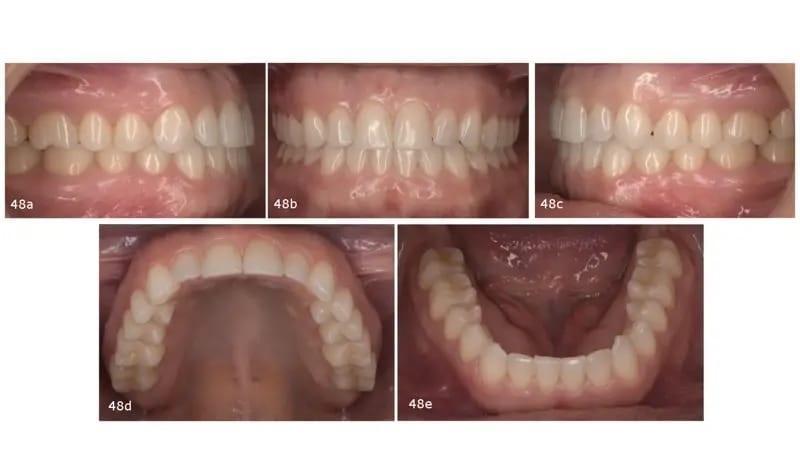

Стоит отметить два аспекта: значительное улучшение улыбки, заключающееся в том, что у пациентки больше не было видно задней десны из-за интрузии задних зубов верхней челюсти; а также более стройный внешний вид лица благодаря расслаблению мышц и уменьшению размера жевательных мышц (фото 47). Были достигнуты взаимоотношения коренных зубов и клыков I класса, а передний открытый прикус был закрыт, что привело к правильным выступу и прикусу. Положительный крутящий момент, приложенный к задним сегментам верхней и нижней челюсти, улучшил форму дуги. Резцы верхней челюсти были наклонены вперед (U1–PP от 105° до 112° после обработки), а резцы нижней челюсти - назад (IMPA от 98° до 93° после обработки; фото 48).

Фото 48a–e: Послеоперационные интраоральные фотографии.